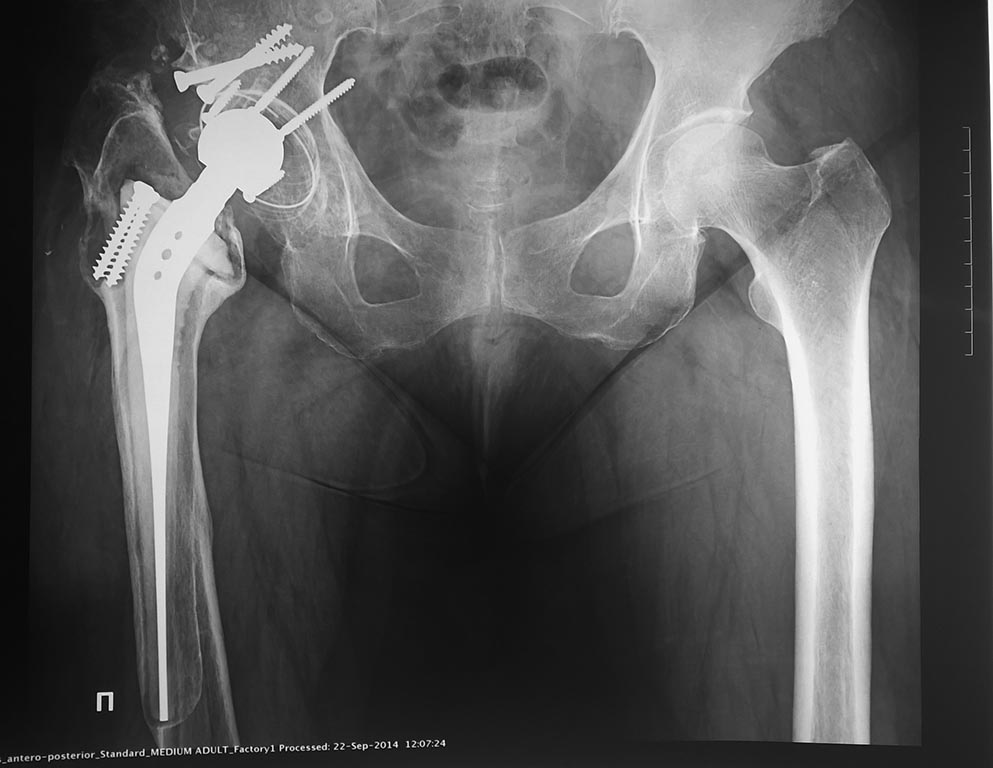

Уважаемые коллеги, добрый день. Хочется поделиться интересным наблюдением, поэтому тему назвал так специально - ортопедическая загадка, а не "Help, что делать?"

Итак, имеем такой вот рентген. Что за протез был установлен 17 лет назад? Фото с ответом выложу в понедельник. Лично я был мягко говоря весьма удивлен.

Это оригинальный RM. Чашку все знают, а вот ногу мало кто видел (как впоследствии оказалось, наверное, к счастью). Имплантировали такие протезы, в основном, в Самаре и Ярославле, понемногу, немного и в Москве

RM - Изоэластик матис

Андрей, это точно изоэластический эндопротез Роберта Матиас, в 90-е годы мы с А.Ф. Лазаревым много таких поставили

Это протез фирмы Матис изоэластик, импрегнированный тиатаном или без титатна - более ранняя версия. Чашка олполи с 2 рожками.